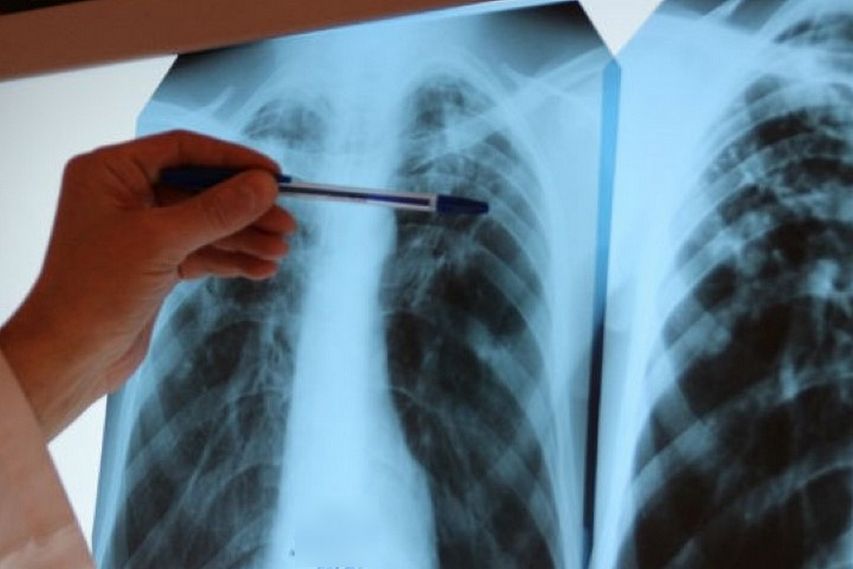

Симптомы и признаки туберкулеза: как распознать заболевание

Раздел: Визуальные уроки